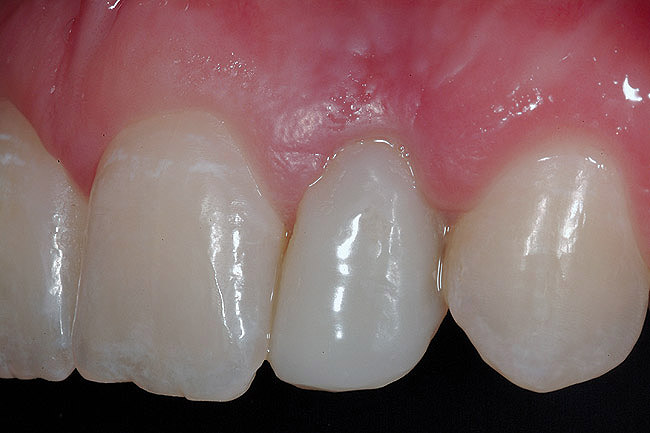

The 3-month postoperative views can be seen in Figure 18 through Figure 20. Note the excellent soft tissue emergence profiles obtained from the properly contoured provisional restorations. After removal of the provisional restorations, further inspection of the contoured emergence profile obtained has been accomplished (Figure 21 and Figure 22). Before impression techniques, transfer copings were seated over the abutment portion of the one-piece implant (Figure 23). A full-arch impression was then taken using medium-body impression material (Take 1 Advanced, Kerr Corporation, Orange, CA) and a regular-body wash material (Take 1 Advanced) to pick up the detail of the emergence profile and impression coping (Figure 24 through Figure 26). After allowing the impression material to set, the impression is then removed from the mouth and inspected (Figure 27). The Take 1 Advanced Medium body has a more rigid set than most other medium materials, so when the coping is placed back in the impression, the possibility of movement during casting is reduced. Please note how the emergence profile obtained has been registered in the impression, and can easily be transferred to the laboratory technician. Laboratory analogues are then placed into the impression coping and forwarded to the laboratory technician for pouring of the casts and final fabrication of the esthetic implant restorations (Figure 28).

Figure 18  3-month postoperative clinical view.

Figure 19  3-month postoperative clinical view, right lateral incisor.

Figure 20  3-month postoperative clinical view, left lateral incisor.

Figure 21  Tissue emergence profiles, right lateral incisor.

Figure 22  Tissue emergence profiles, left lateral incisor.